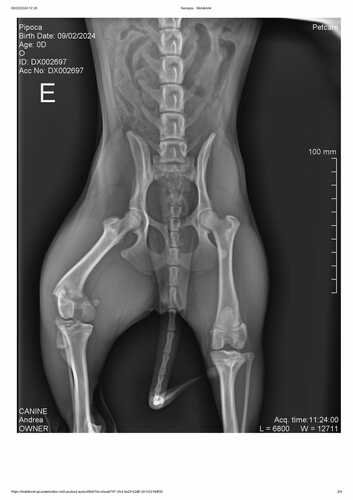

Certo dia, apareci só de manhãzinha. Minha mãe ficou o dia inteiro me procurando e preocupada comigo até que, à noite, ela viu uma publicação no Facebook da sua amiga, repostando a foto da Pipoca. Na legenda dizia que eu tinha sido atropelada e que eu estava no canil. Minha família ficou desesperada e, logo no outro dia, foram me buscar no canil, me adotaram (mesmo eu não dando muito certo com a Pituca), fizeram um RX no meu quadril e o resultado foi que quebrei o fêmur. Minha nova família me levou pra casa e fiquei tomando alguns remédios para dor enquanto minha mamãe providenciava veterinário e cirurgia pra mim.